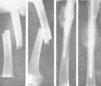

Figura 1. Fractura tercio superior fémur transversal, reciente, enclavijamiento cerrado. La misma, una vez enclavijada; correcta reducción e inmovilización que permiten la marcha sin ningún otro procedimiento secundario de inmovilización.

Figura 2. Fractura transversal tercio medio tibia, sin desviación, peroné íntegro, enclavijamiento cerrado; fue uno de los primeros casos tratados, y a los tres meses reanudaba el trabajo; un solo clavo mantuvo una perfecta inmovilización.